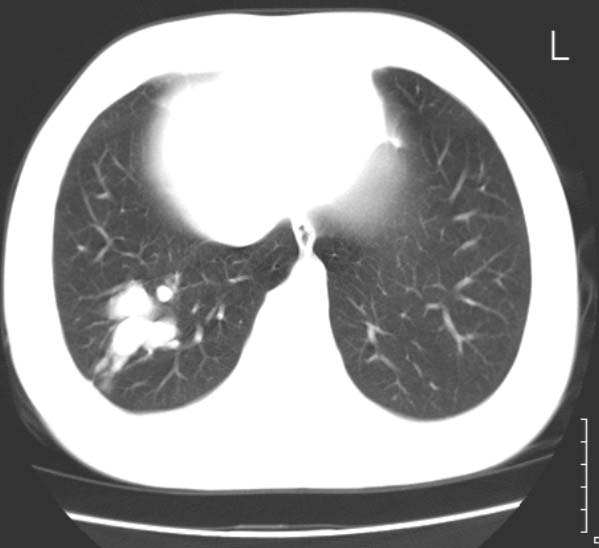

标题: CT25816:胸部CT,请会诊。

女 19岁,发热,咳嗽

考虑右下肺动静脉畸形,建议增强进一步检查。

1、右下肺动静脉畸形?2、右下肺囊肿?建议ct增强扫描。

典型的支气管粘液栓,建议抗炎治疗复查,会有变化的。

考虑右肺下叶支气管扩张并黏液嵌塞。